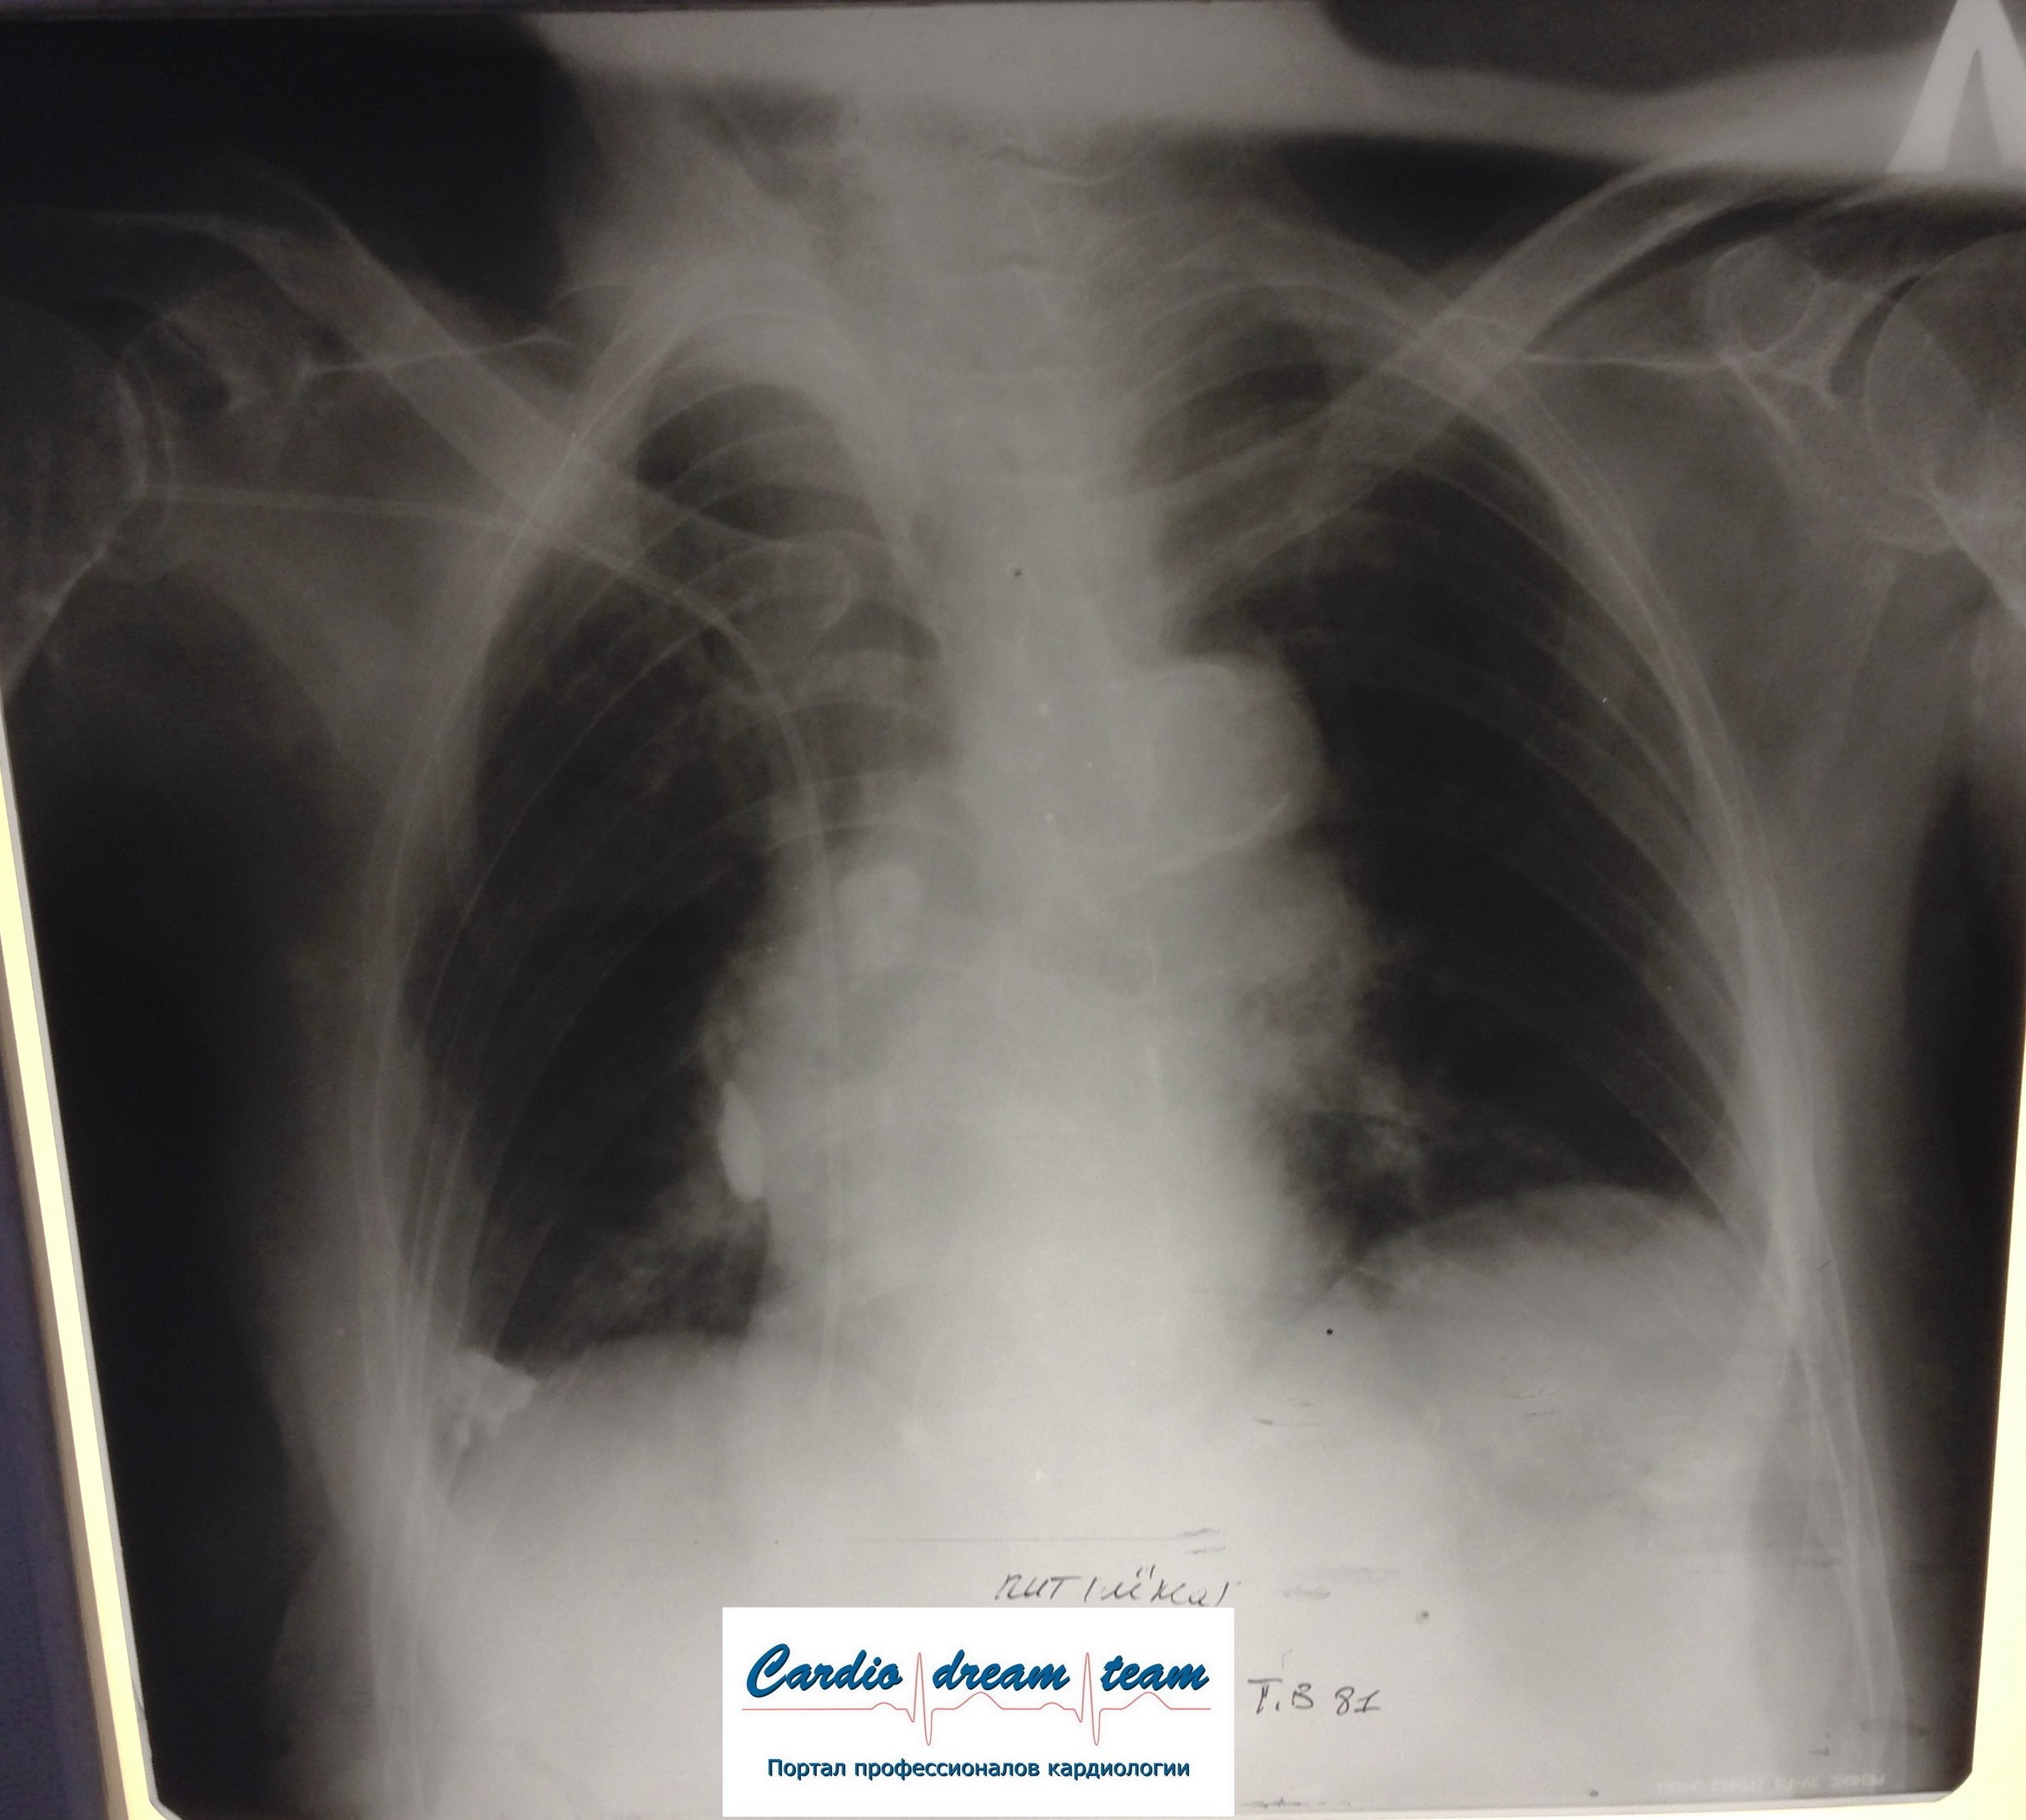

Больная согнула руку в момент съемки

Неправильное положение тела при съемке

Есть только кальцинаты, остальное кажется